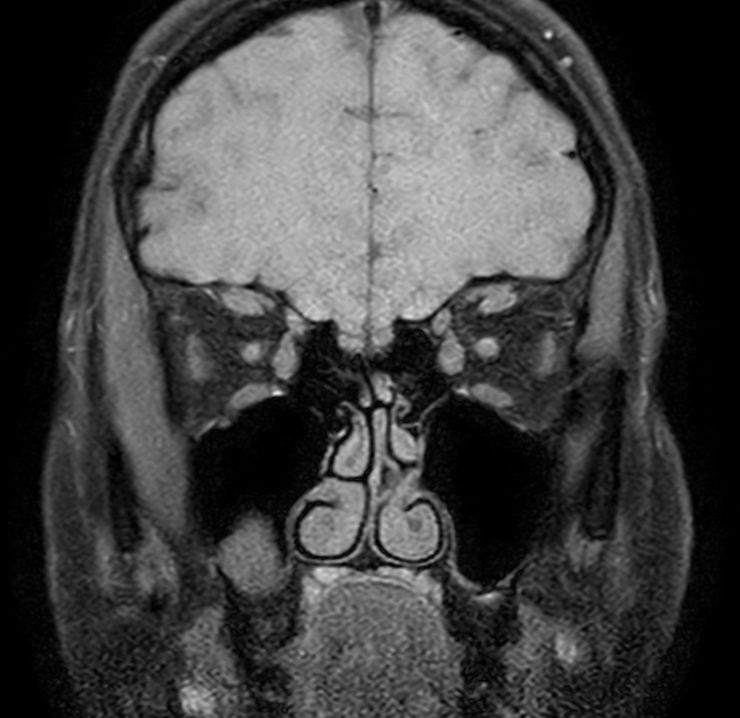

3D VIEW - T1w TSE (coronal reformat)

Post-Gado